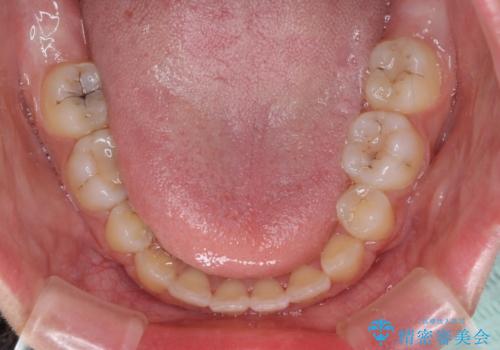

- 上下の出っ歯を気にして来院された患者様です。

口元を積極的に引っ込めるために、上下左右の第一小臼歯を4本抜歯することとしました。

前歯部の突出と開咬は、舌突出癖によるものでしたので、舌のトレーニングをしっかりと行っていただき、1年半程度と短期間で治療を終えることができました。